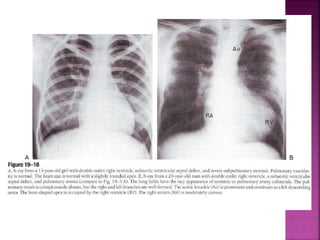

 CXR in DORV sub Ao VSD low PVR similar to

non restrictive peri mem VSD with high Qp

 Thymus is present in DORV TGA end of spectrum

unlike D-TGA wherein thymus typically absent

 Pulmonary trunk prominent (side by side

arteries)

 LA LV prominent in volume overload

 RA RV prominent with CCF

 Lung fields oligemic before fall in neonatal PVR

and with onset of pulmonary vascular disease

(semblance with non res VSD with EISENMENGER)

subaortic VSD

Guideline DORV

parasternal long axis

Ao

LV LA

Subcostal TEE

RV

PA

subaortic VSD with severe subpulmonary obstruction